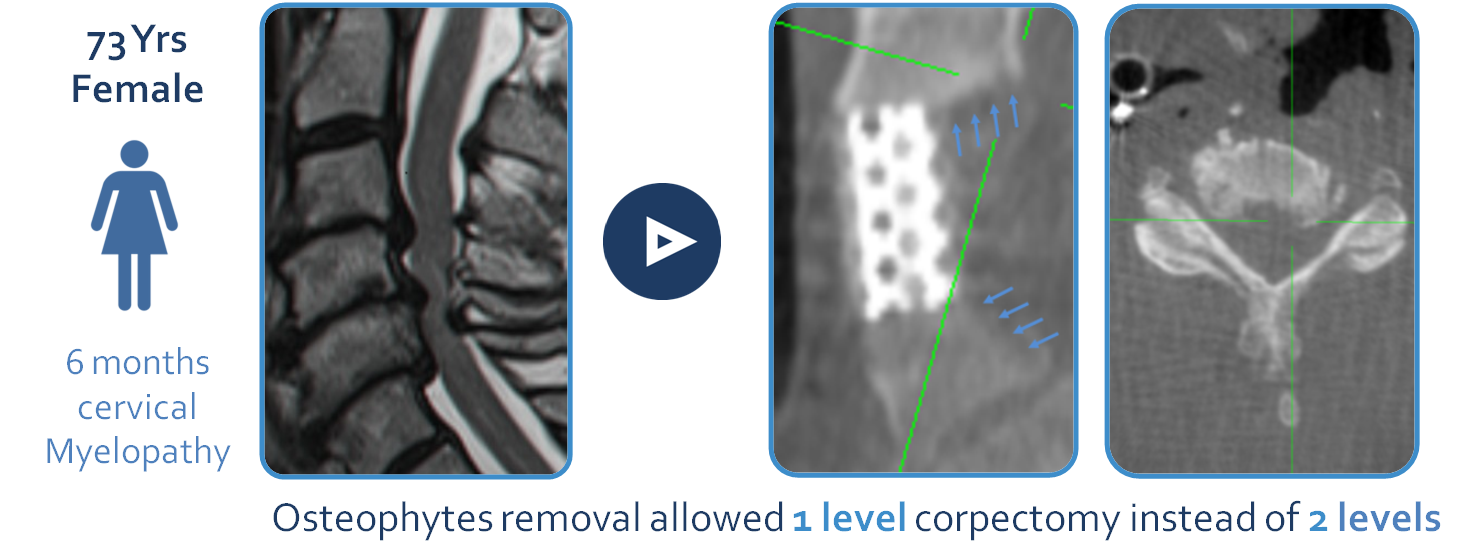

CASE #1 – Cervical- 73 year old female – Cervical Myelopathy